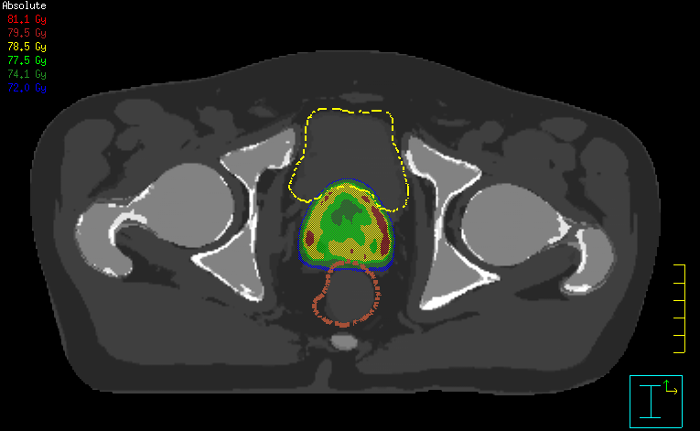

With its exceptional soft-tissue visualization capabilities and wide range of image contrasts, MRI has become a powerful tool to help more precisely define tumor boundaries. This is particularly important as it has been established that there is a high degree of uncertainty in target volume delineation, and it is even reported to represent the largest uncertainty in the entire radiotherapy process for most tumor sites**. Better visualization of the target area and nearby organs-at-risk is a key factor in enhancing target volume delineation. MRI’s expanding role also can be attributed to its functional imaging capabilities, which can inform both target characterization and treatment response.

Our innovative MRCAT (MR for Calculating ATtenuation) clinical applications lets you plan radiation therapy using MRI as primary imaging modality. Within just one, fast MR exam, MRCAT provides both excellent soft-tissue contrast for target and OAR delineation and CT-like density information for dose calculations.

This not only extends the benefits of MRI’s excellent soft-tissue contrast to radiotherapy planning, but it also eliminates arduous, error-prone CT-MRI registration from the process, reducing uncertainties and complexity.